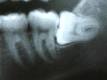

· Nah sekarang bukannya nakut-nakutin, tapi ada pada beberapa orang kasus seperti ini, gigi paling belakang nongol tidak pada posisi yang benar, dalam bahasa kedokteran (impacted). Terjadi bisa karena struktur rahang kita yang sudah tidak cukup lagi untuk menampung gigi itu, Bisa juga memang benih gigi berada pada posisi yang tidak tepat, (ini saya baca dari beberapa Buku), berikut ini beberapa contoh gambar yang menunjukkan impaksi pada gigi yang paling belakang bawah..

Saat menimbulkan masalah tentunya periksakan ke Dokter Gigi terdekat, Biasanya akan dilihat secara langsung yang pertama kali dilakukan, Jika tidak bisa maka akan diambil dengan foto X ray gigi, supaya kelihatan jelas semuanya.

Perawatan yang biasa dilakukan oleh Dokter Gigi yaitu mempertahankan atau cenderung mengangkat gigi tersebut, dengan pertimbangan Dokter Gigi bagaimana yang terbaik.

Untuk kasus impaksi gigi seperti diatas kebanyakan dicabut, dan kadang pada beberapa kasus yang sulit bisa jadi akan dilakukan operasi kecil (odontectomi/pencabutan gigi paling belakang dengan jalan operasi). Tapi jangan takut dan ngeri, demi kebaikan kita juga to, lebih baik ngeri sekali daripada ngeri seumur hidup gara-gara sakit gigi, Mau!!